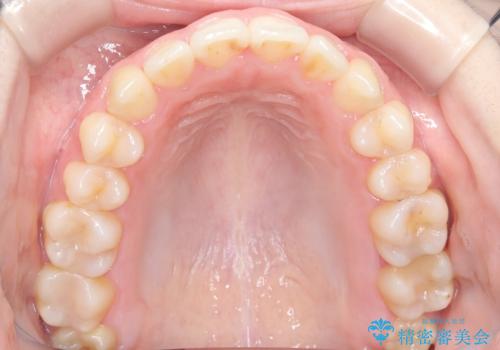

前歯のガタツキ、前歯の噛み合わせ(開咬)をインビザライン治療で治しました

- 前歯のがたつき、噛み合わせが気になるとのことで来院された患者様です。

インビザラインを使用して治療しました。

前歯がしっかり噛んでない状態(開咬)を治すために、前歯にゴムをかける必要があります。ゴムかけは患者様にご協力していただきます。